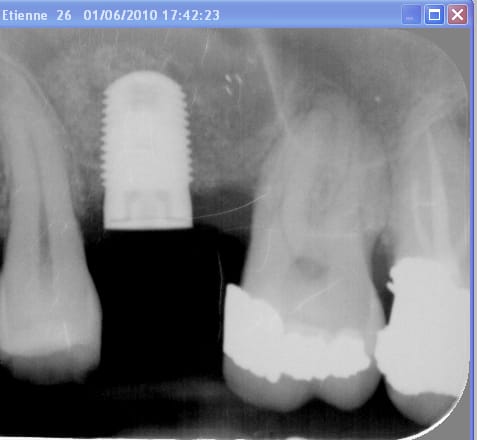

Le cas date de 2010, le sinus est traité par élévation crestale + mise en place de 2 mb de PRF dans le "trou" avant de combler au RTR et en dernier os récupéré du forage pour espérer qu'il reste contre l'implant.

J'ai pas pu enlever le prénom mais vous avez les dates dans l'ordre

La radio postée hier est un "contrôle à 6 ans avant d'implanter en 14

Il n'y a que du PRF ?!! et un peu d'os de forage mais vu la hauteur initial.....

C'est troublant. C'est bluffant de voir la quantité d'os formé avec juste du PRF mais ce qui me "chagrine" c'est l'aspect radiologique un peu dégueu, comme si t'avais mis des granules de synthétiques.

Je me suis mis au PRF depuis peu et je suis vraiment curieux de voir ce qu'on faire avec. C'est encourageant parce que tu nous présente un cas vraiment limite que beaucoup (dont moi) aurai traité par voie latéral. En plus avec le PRF tu minimises le principal défaut du Summer, à savoir l'impossibilité de contrôler l'intégralité de ta membrane.